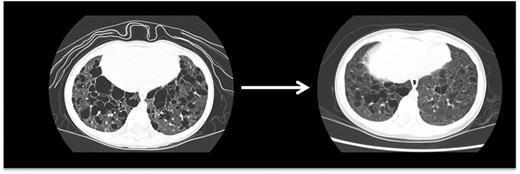

Evaluating disease activity and response to therapy

Pulmonary LCH. This high-resolution CT scan demonstrates pulmonary lesions and associated cysts in a 3-year-old girl with high-risk LCH. LCH lesions were cleared from lung parenchyma following cladribine therapy, though some cystic disease was irreversible.